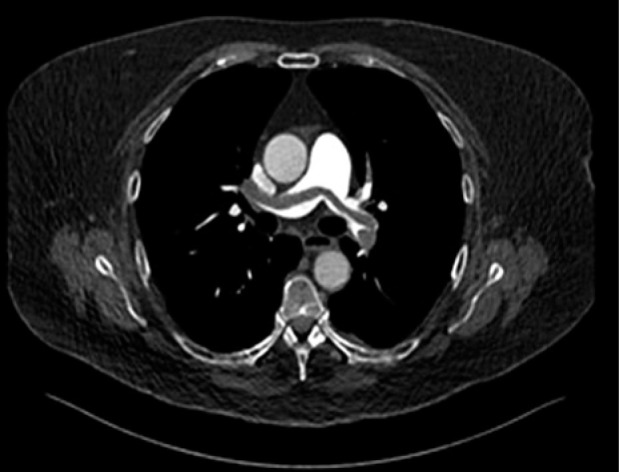

Case presentation: This case series reported three women, who experienced near-fatal saddle pulmonary embolisms shortly after undergoing high-dose-rate brachytherapy for locally advanced cervical cancer. In one patient, pulmonary saddle embolism led to hypovolemic shock due to intra-abdominal hemorrhage post-resuscitation, necessitating emergency decompressive laparotomy. Another case was complicated by neurological symptoms consistent with a stuttering stroke, following mechanical pulmonary thrombectomy.